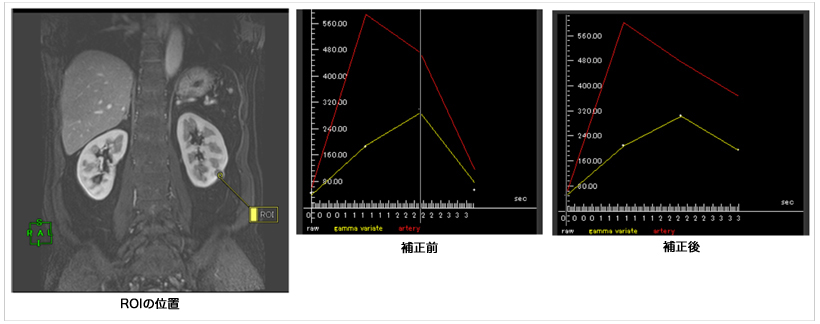

ダイナミック撮影ではターゲットの造影パターンによって腫瘍診断が行われます。新たに開発されたダイナミック4D解析は,対象ROIのタイムデンシティカーブを描画し,血流速度などを評価できるソフトウェアです。すべての時相のデータ間で非剛体レジストレーションを行うことによって,画像全体を補正し,より正しい値を抽出できるシステムとなっています(図7)。すべての時相に対する画像補正はワンクリックで行うことができるため高い再現性があります。補正されたデータを使いカーブフィッティングを行うことで,ダイナミックデータから血流速度値を算出できるシステムを構築中です。

図7 ダイナミック 4D解析 補正を施すことでより精度の高い解析を行うことができます。